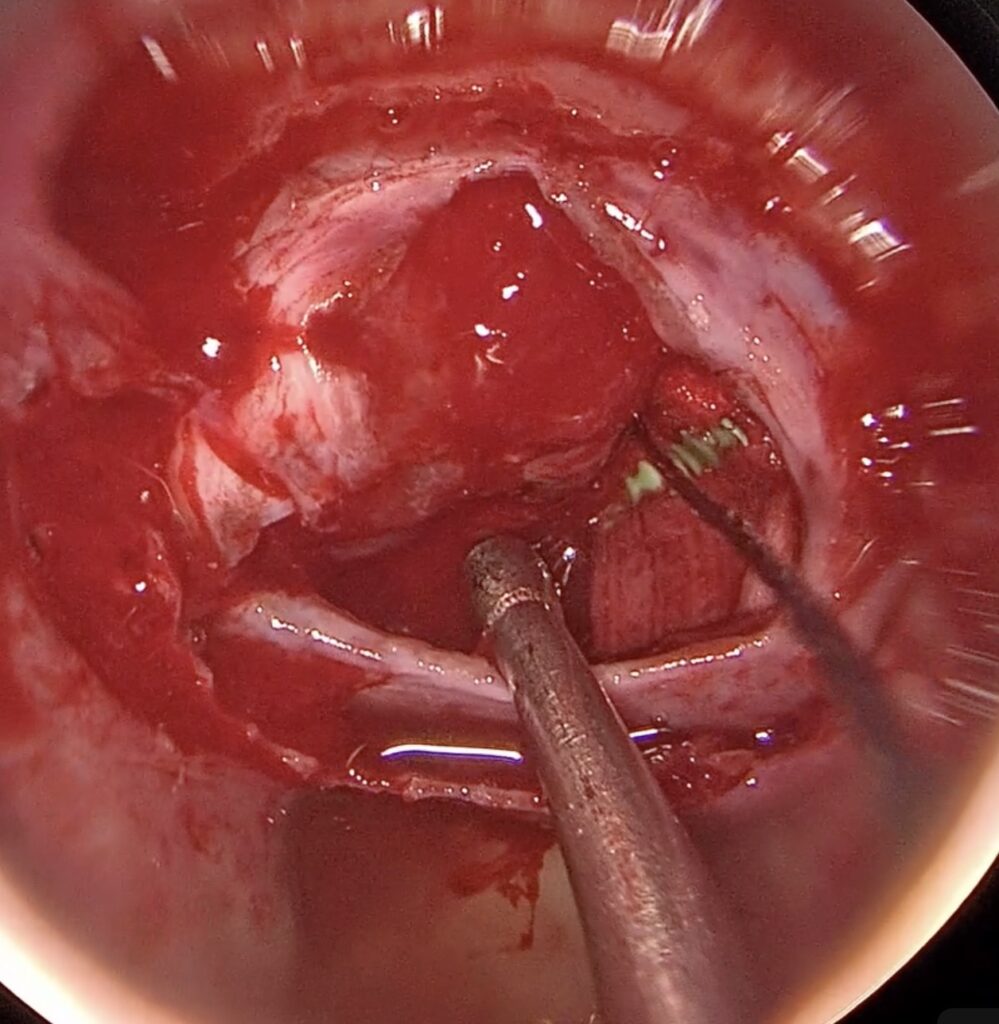

37歳女性 下垂体線腫を内視鏡手術しました。両耳側の視野欠損が回復しました。

若いですが、視野狭窄で発見された下垂体線腫を内視鏡で摘出しました。トルコ鞍前壁を十分に削除することで、上方の腫瘍残存をなくし、術後出血を防止できました。一過性に尿崩症が出現しましたが、コントロールされ退院されました。